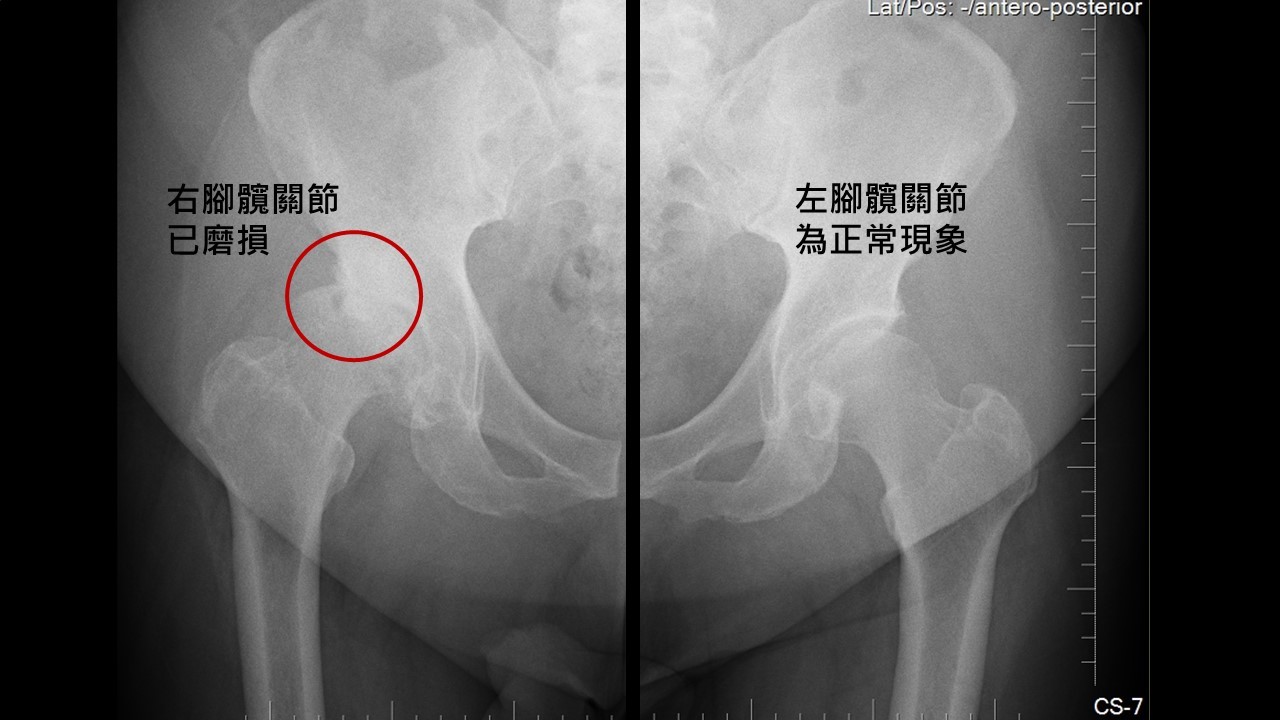

人工髖關節置換手術案例 陳奕霖醫師 永和耕莘醫院骨科醫師 永和骨科推薦